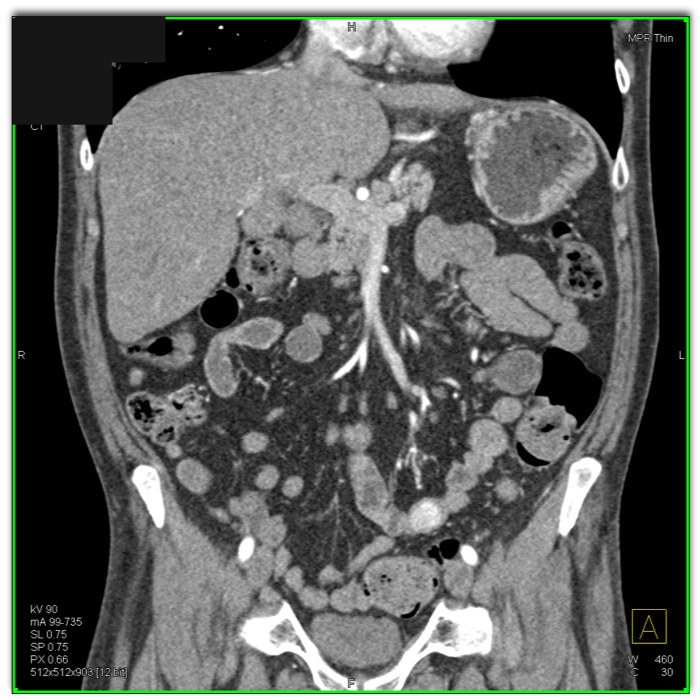

1) The likely cause for a GI bleed in this patient is?

AV malformation

diverticular disease

small bowel tumor (vascular)

lymphoma